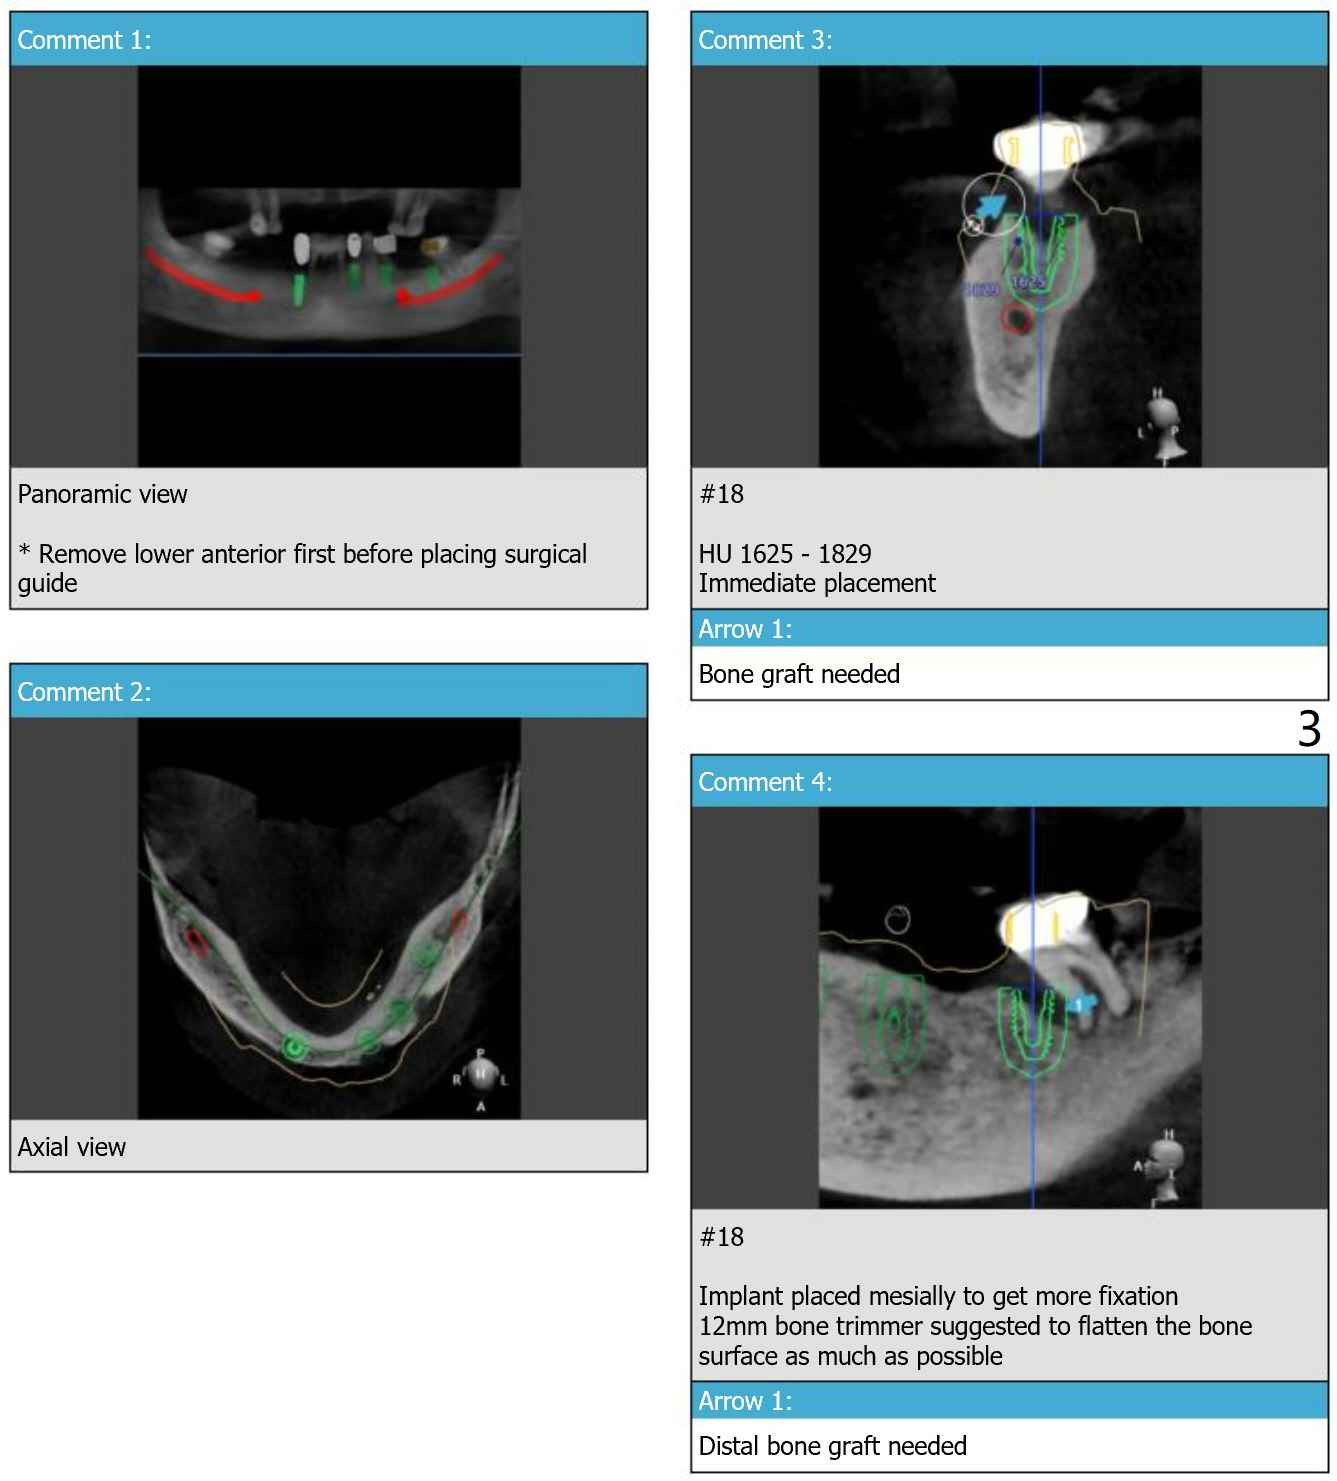

Guide 2 Using #20,22,27 Sleeves as Anchors

For placement of implant at #18.

Return to Lower Arch Immediate Implant, Trajectory